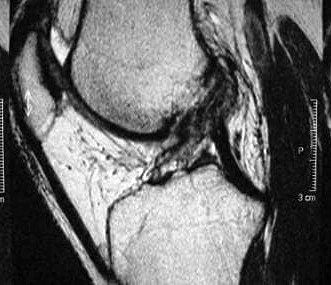

Which ligament is tear in this image of a patient?

ACL